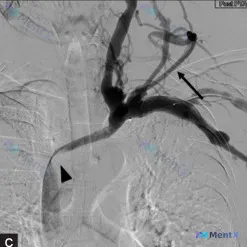

看到这个病例,整理了一下完整的分析思路,分享给大家。 病例基本信息 - 患者:53岁女性 - 主诉:右臂间歇性沉重、感觉异常2个月,近2周画壁画时反复出现头晕,伴恶心、视力模糊,喝果汁后症状消失 - 既往史:高血压、2型糖尿病、高胆固醇血症,目前用药:二甲双胍、格列吡嗪、依那普利、阿托伐他汀 - 体...